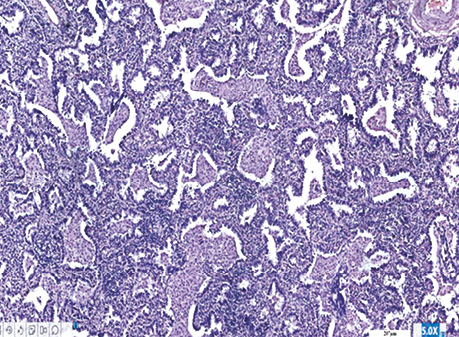

Аналіз гістологічного дослідження плоскоклітинного РЛ різного ступеня диференціювання також дозволив виявити деякі структурні особливості (рис. 4–6). У 1 хворого встановлено поширений пухлинний процес — виявлені пухлинні вузли в усіх 3 видалених під час операції частках правої легені, ще у 1 хворого новоутворення було без чітких периферичних контурів. За біопсійним матеріалом 1 хворого встановлений плоскоклітинний РЛ, а за операційним — аденосквамозний тип. Крім того, детальне вивчення гістологічної структури плоскоклітинного РЛ у всіх 15 хворих дозволило виявити ділянки з ростом пухлини в альвеолах з характерним напрямком росту від базальної мембрани до її центру.

Рис 6. Плоскоклітинний рак. Ріст пухлини в альвеолах. Гістологічний препарат, гематоксилін і еозин, × 200